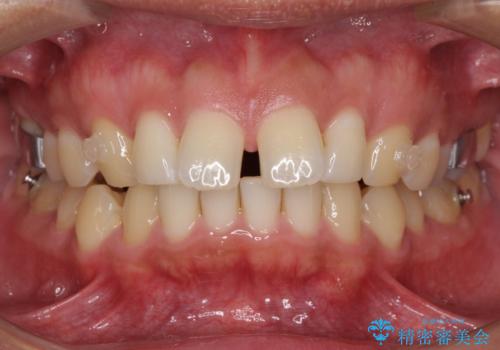

- 上顎前歯の突出感とすきっ歯を気にして来院された患者様です。

奥歯の咬み合わせを見ると、下顎に対して上顎が前方に位置していたため、補助装置により上顎歯列全体を後方に移動させ、その後インビザラインにて歯列全体を整えることとしました。